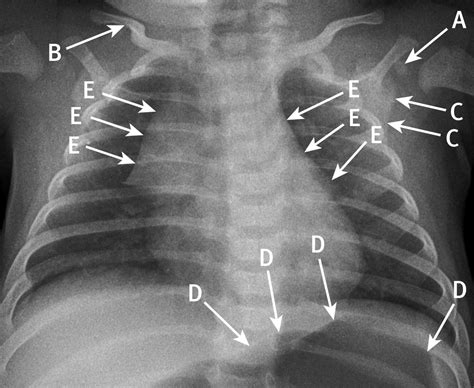

• Diagnosis of Respiratory Conditions: Conditions like pneumonia can be detected through chest X-rays, allowing for timely intervention.

Pneumonia Chest X-rays can detect pneumonia, an infection of the lungs, by showing areas of inflammation or fluid buildup.

• Radiologist Review: The X-ray images are reviewed by a radiologist, who will look for any signs of fractures, infections, or other abnormalities.